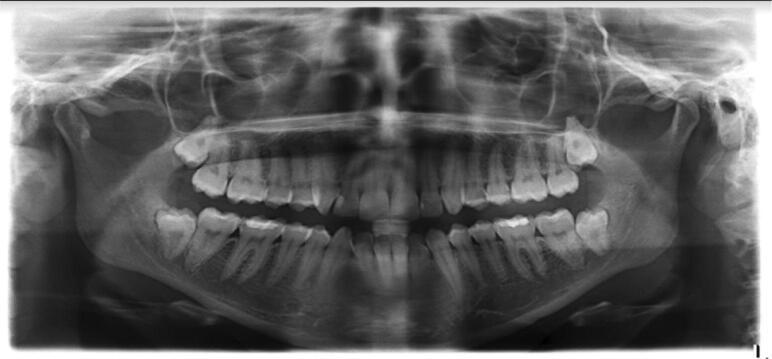

In this cross-sectional study, 1200 panoramic radiographs (50% males and 50% females) were retrieved from the electronic clinical records of patients at the College of Dentistry, Jazan University from December 2014 to December 2016, and impacted third molars were evaluated. Data on clinical and radiographic presentation were analyzed.

Overall, there were 291 (24.3%) patients with impacted third molars among 1200 radiographs. The distribution of impacted third molars according to the number of impacted teeth was as follows: one impaction in 121 (41.6%); two impactions in 90 (30.9%); three impactions in 42 (14.4%); and four impactions in 38 (13.1%) patients. There was a high prevalence of all impaction types among females (54.5%). Maxillary vertical angulation was most common (50%) followed by mandibular mesioangular angulation (48.3%). The depth of impaction in maxillary teeth was higher than in mandibular teeth. Pain was uncommon (4.5% of patients).

Clinically, vertical impaction in the maxilla was present in 50% of patients because of limited posterior space, and mesioangular angulation in the mandible was present in 48% of patients because of inadequate space between the ramus and the second molar. These findings are similar to other reports. Vertical impaction of the maxillary wisdom tooth is mostly related to the discrepancy between the mesiodistal size of the tooth crown and the limited retromolar space.